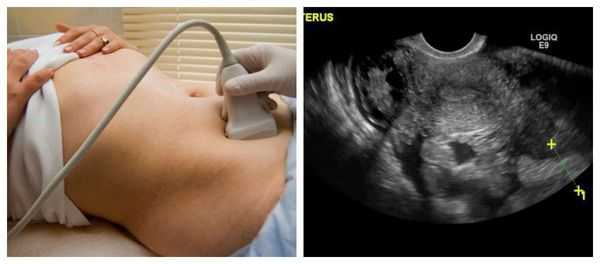

- УЗИ малого таза. Определяется матка нормальных размеров. Напрямую разрыв яйцевода при помощи ультразвука диагностировать нельзя, косвенным признаком патологии является скопление жидкости в малом тазу.

- Ультразвуковое исследование. Ультрасонография является основным методом выявления эктопической беременности (в том числе прогрессирующей). Особую ценность представляет трансвагинальное УЗИ, позволяющее визуализировать плодное яйцо уже на первых неделях гестации. Среди диагностических критериев заболевания - признаки гравидарной гиперплазии эндометрия при отсутствии эмбриона в матке, объёмное образование в области трубы, скопление жидкости позади матки.